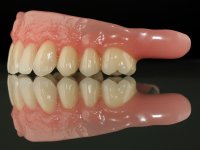

Then, the teeth were mounted in the screwed record bases and function and aesthetics were clinically evaluated. After these evaluations, the dental technician develops silicone walls that guide the fabrication of the milled bars. The precise passive fit of the bars was checked clinically and with radiographs. Then, a pick-up impression with an individualized tray was done to achieve a functional impression of the soft-tissues.

The overdentures with a metallic framework were fabricated over the bars, according to the silicone walls previously made. Before finishing the dentures, a new functional and aesthetic evaluation of the teeth was done, together with a new jet-bite registration to allow small occlusal adjustments.